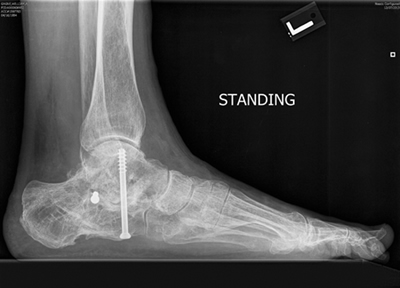

The proposal was to completely reposition my collapsed heel and limit the fusion to just one joint so that I can maintain mobility. Rehab put me out for a while but now I can wear shoes, walk straight, work, hike, snowshoe and exercise again. In my opinion, Dr. Leavitt is not only a cutting edge, top notch doctor but a dedicated craftsman who takes pride in and enjoys his work. As busy as his office is you'll feel like you are his only patient. Also the other doctors and staff at New England Baptist Hospital were excellent to deal with before, during and after surgery.

I also wish to commend the other doctor involved in Bill's surgery, Dr. Hervey Kimball. One of the essential ingredients in the surgery was the use of a piece of Bill's hip, which did many wonderful things including giving Bill back height, repositioning the heel and fusing the joint thus stopping the pain. Dr. Kimball is a hand surgeon who is often called upon to take pieces of the hip to be used in joint fusions in the foot and hand. He was kind and meticulous and Bill's hip hurt very little after the surgery. -- Dr. Ken Leavitt